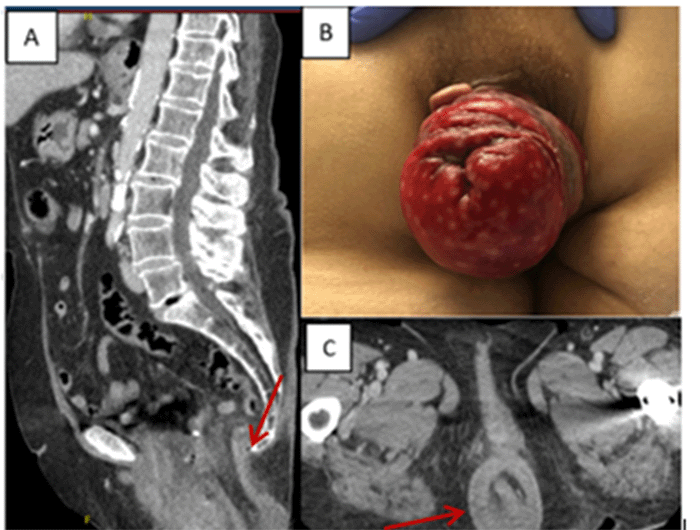

The patient presented with mild abdominal pain, and physical examination revealed an irreducible, circumferential, full-thickness prolapse (Figure 1). A positive sulcus sign (Figure 2) strongly suggested coloanal intussusception rather than rectal prolapse. CT imaging of the abdomen and pelvis showed what appeared to be a prolapse of the rectum with associated surrounding inflammation (Figure 1). An attempt to reduce the edema and facilitate reduction using table sugar was unsuccessful. Given the diagnosis of incarcerated coloanal intussusception, the patient was consented for a combined perineal and abdominal approach by a colorectal surgeon.

Figure 1. Patient Presentation. Published with Permission

A) Sagittal CT demonstrating coloanal intussusception; B) clinical presentation of coloanal intussusception in the emergency department; C) axial CT view of the intussusception

The patient, under general anesthesia, was positioned supine with legs in stirrups for easy access to the perineum. Initial manual reduction of the rectal intussusception via the perineum failed, necessitating a low, midline laparotomy. The rectosigmoid junction was identified as the lead point, with patchy ischemia on the proximal rectal wall. Combined transabdominal and perineal reduction attempts were unsuccessful. Therefore, a perineal approach was used to circumferentially transect the distal rectum 3-4 cm from the anal verge (Figure 2). After changing surgical attire, the transabdominal approach mobilized the sigmoid colon, successfully reducing the remaining incarcerated bowel into the abdomen. Further rectal mobilization occurred below the ischemic areas. A low anterior resection was performed due to rectal edema and size mismatch, followed by a side-to-end hand-sewn anastomosis. A negative leak test via flexible sigmoidoscopy and a 2-0 suture rectopexy concluded the procedure.